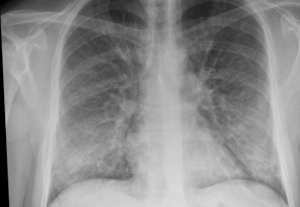

Ernesto Estrada es un investigador de la Universidad de Zaragoza y de la Fundación Agencia Aragonesa para la Investigación y el Desarrollo (ARAID). Recientemente ha publicado en la revista Chaos un estudio sobre los casos graves de Covid-19. Ha explicado que el daño puede extenderse desde los pulmones hacia otros órganos, como el corazón, el hígado, los riñones y partes del sistema neurológico, sin afectar a otros.

Una vez dentro de una célula humana, las proteínas del virus interactúan con las del cuerpo, permitiendo que sus efectos se desarrollen. El Covid-19 daña solo un subconjunto de órganos, lo que le indica que debe haber una vía diferente para su transmisión. Para descubrir una ruta plausible, Estrada consideró los desplazamientos de proteínas predominantes en los pulmones y cómo interactúan con proteínas en otros órganos.